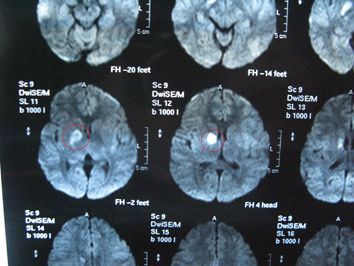

任何人:这就是你妹妹脑子里长的那个肿瘤。

任何人:现在还太小了,我们这边根本就无法切除,我们这边也不敢动手术。

任何人:对的,因为我们现在还在观察是良性的还是恶性的